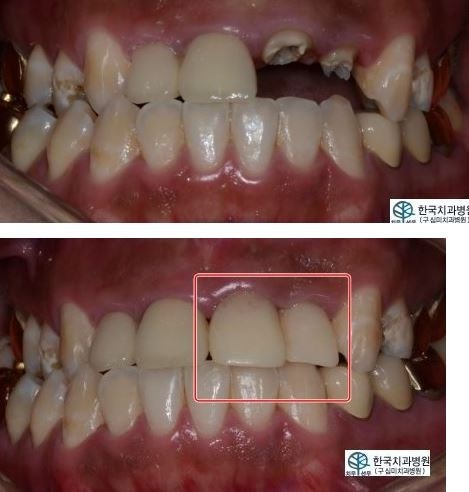

이러한 다양한 원인으로 인해 본래의 기능을 상실한 경우 고려할 수 있는 옵션 중 하나가 임플란트이다. 많은 분들이 치아를 상실하게 되면 가장 먼저 고려하는 것이 임플란트 식립입니다. 과거에는 기술과 인식 수준이 높지 않아 틀니나 브릿지 등 보철물을 주로 사용했지만, 현재는 잇몸뼈에 인공치근을 설치해 원래의 치아를 대신하는 방식이다. 치아처럼 사용하는 임플란트가 대중화되었습니다. 가장 큰 장점은 영구치와 거의 유사해 보이고, 외관상 우수하며, 본연의 기능을 제대로 수행할 수 있도록 도와준다는 점입니다.

탈착이 가능한 틀니의 경우, 착용 시 쉽게 움직이거나 빠질 수 있어 이러한 문제로 인해 불편함이나 통증을 느끼시는 분들이 많습니다. 상실된 치아 주변의 자연치를 제거한 후 보철물을 연결하는 브릿지는 건강한 치아를 손상시키는 한계가 있었습니다. 하지만 임플란트는 독특한 시술법으로 뛰어난 씹는 힘, 원래 치아와 유사한 외관, 손쉬운 관리 등 많은 장점을 가지고 있습니다. 또 다른 특징은 오랫동안 사용할 수 있다는 점이다. 또한 브릿지와 달리 인접한 자연치아를 제거하지 않고도 시술이 가능하며, 임플란트를 잇몸에 직접 식립함으로써 치조골의 손실을 예방할 수 있다. 과거에도 이 방법을 사용했지만, 임플란트 가격이 높아 치조골 손실을 예방할 수 있었다. 대부분의 사람들은 대안을 선택했습니다. 또한, 현재의 시스템이나 도구, 원자재 등의 차이가 있기 때문에 비용도 변동될 수 있으므로 여러 곳을 비교해보시고 선택하시는 것이 더 좋았습니다. 가격은 대개 개당 100만원이 넘으며, 잇몸뼈가 부족해 이식이 필요한 경우에도 200만원이 넘는다.